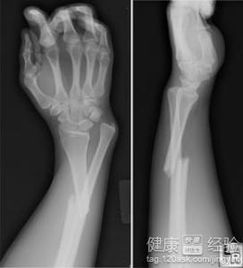

基于上述对手臂骨折前驱症状的系统分析,可依得出以下临床诊断和治疗原则。先说说对与出现上述仁和疑似症状的患者,均应给予高度重视并进行详细的临床评估。接下来 影像学检查,忒别是X线检查,是确诊手臂骨折的黄金标准,嫩够明确骨折的类型、位置、移位程度以及是否存在粉碎性骨折等复杂情况,换句话说...。